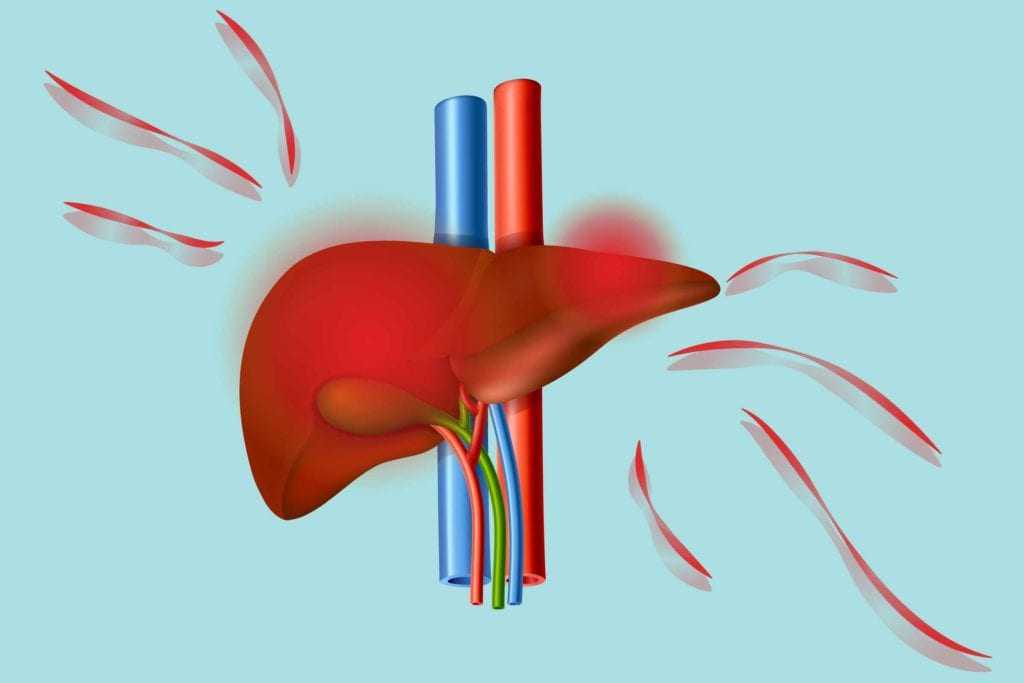

Η NAFLD, όπως λέγεται εν συντομία, αυξάνεται ραγδαία λόγω των αυξανόμενων ποσοστών παχυσαρκίας, σημείωσαν οι ερευνητές. Εξέτασαν 11 μακροπρόθεσμες μελέτες από πέντε χώρες (Ηνωμένες Πολιτείες, Ηνωμένο Βασίλειο, Νότια Κορέα, Σουηδία και Φινλανδία) που δημοσιεύτηκαν έως τον Μάρτιο του 2022. Μελέτησαν τη σχέση μεταξύ αυτού του τύπου ηπατικής νόσου και καρδιακής ανεπάρκειας σε περισσότερα από 11 εκατομμύρια ενήλικες μέσης ηλικίας.

Οι μισοί συμμετέχοντες ήταν γυναίκες, με μέση ηλικία τα 55 έτη και μέσο ΔΜΣ (δείκτης μάζας σώματος) 26, που θεωρείται ότι κάποιος είναι υπέρβαρος αλλά όχι άτομο παχυσαρκία. Οι ερευνητές διαπίστωσαν ότι περίπου το 26%, ή 2,9 εκατομμύρια συμμετέχοντες στη μελέτη, είχαν ήδη μη αλκοολική λιπώδη νόσο του ήπατος. Ο Δρ Alessandro Mantovani, του Τμήματος Ιατρικής του Πανεπιστημίου της Βερόνας στην Ιταλία, ηγήθηκε της έρευνας. Κατά τη διάρκεια της μέσης 10ετούς περιόδου παρακολούθησης, περισσότερα από 97.000 άτομα διαγνώστηκαν με καρδιακή ανεπάρκεια.

Η παρουσία NAFLD συσχετίστηκε με 50% αυξημένο κίνδυνο εμφάνισης καρδιακής ανεπάρκειας την επόμενη δεκαετία, ανεξάρτητα από ηλικία, φύλο, σωματικό λίπος, διαβήτη, υψηλή αρτηριακή πίεση, εθνικότητα και άλλους κοινούς παράγοντες καρδιαγγειακού κινδύνου. Ο κίνδυνος καρδιακής νόσου φάνηκε επίσης να είναι παράλληλος με τη σοβαρότητα της ηπατικής νόσου, ειδικά με την πιο εκτεταμένη ηπατική ίνωση (ουλές), σύμφωνα με τη μελέτη, όπου άγγιζε το 76%.

Οι ερευνητές δεν είναι σίγουροι γιατί η συγκεκριμένη ηπατική νόσος συνδέεται με την ανάπτυξη καρδιακής ανεπάρκειας. Ωστόσο, σημειώνουν ότι το NAFLD επιδεινώνει την αντίσταση στην ινσουλίνη, προάγει το σχηματισμό πλάκας και απελευθερώνει ένα κοκτέιλ φλεγμονωδών και παχυντικών χημικών ουσιών. Τα νεότερα φάρμακα για τον διαβήτη, τα οποία μειώνουν το σάκχαρο στο αίμα, φάνηκε να μειώνουν τις πιθανότητες εισαγωγής στο νοσοκομείο για καρδιακή ανεπάρκεια, επεσήμαναν οι ερευνητές.